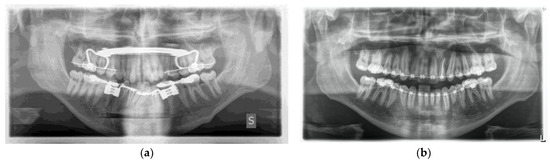

One week post-op, an OPT (Orthopantomography) X-ray was performed, which showed the adequacy of the osteotomy and the preservation of dental roots. Three years later, at the end of orthodontic alignment, the second surgical step was carried out (Figure 11a,b).

Figure 11.

(a) Postoperative Orthopantomography X-ray; (b) post orthodontic alignment.

The day following the surgery, a follow-up OPT X-ray was requested, which displayed the resection area and the integrity of the lower and upper borders of the mandible, in accordance with the preoperative virtual planning (Figure 15).

Figure 15.

Postoperative OPT X-ray showing the resection area and the integrity of the lower and upper borders of the mandible.